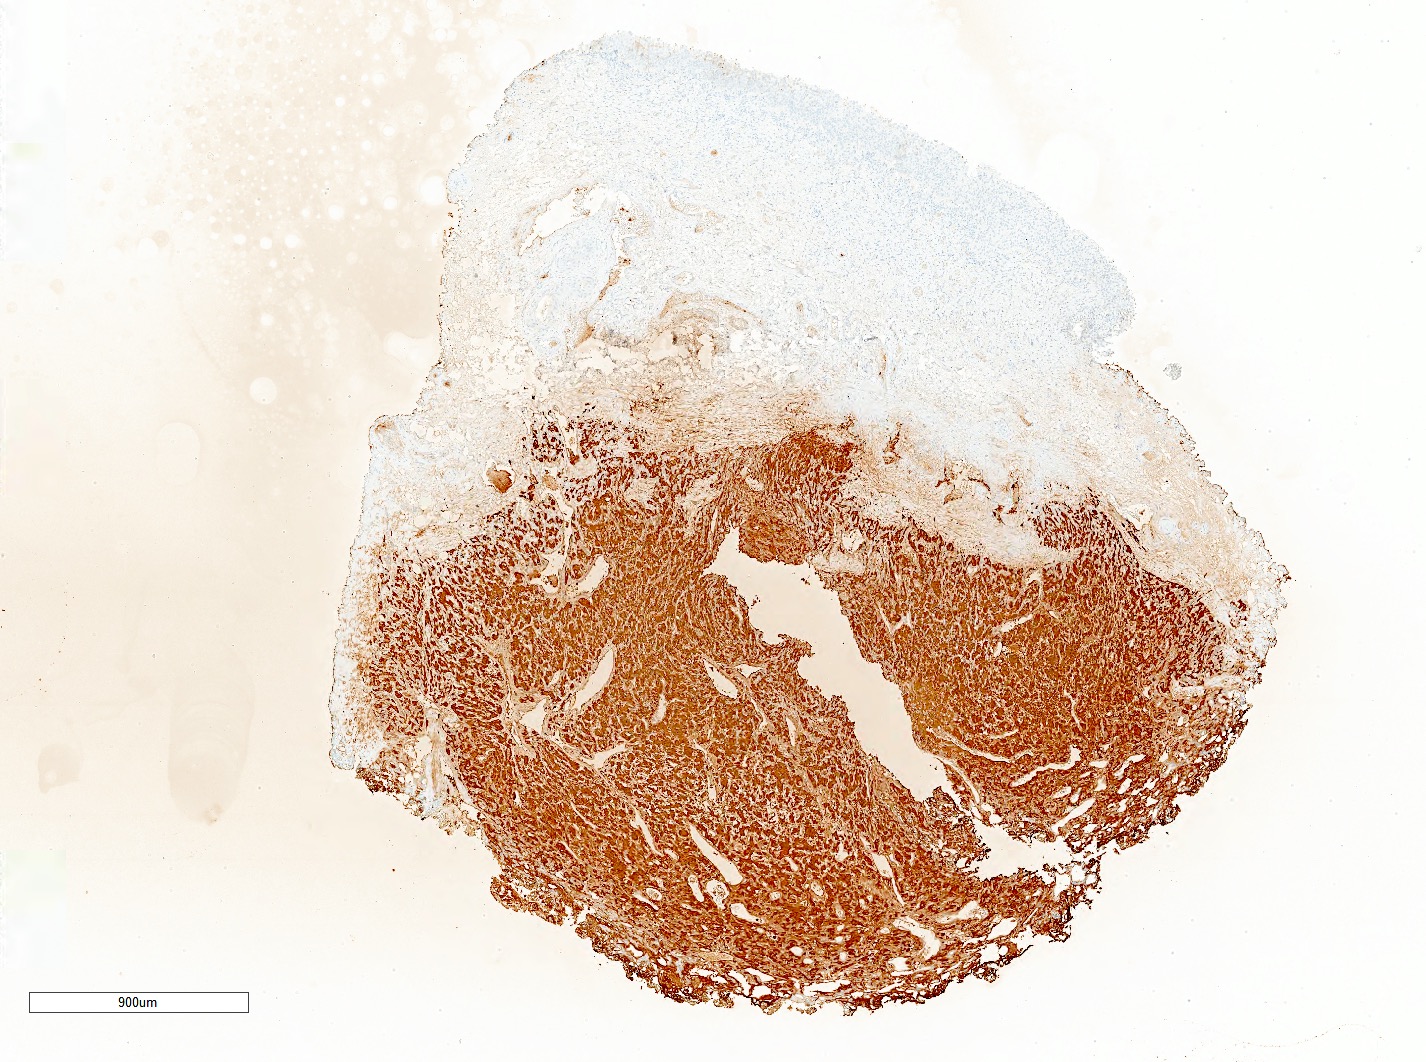

- Tumor cells are positive for GATA3 and neuroendocrine markers while negative for keratins; sustentacular cells are positive for S100 and SOX10

Contributed by Theodorus H. van der Kwast, M.D., Ph.D., Michelle R. Downes, M.D., Debra L. Zynger, M.D. and David Cohen, M.B.B.Ch., M.D.

Positive stains

- INSM1 (diffuse), chromogranin A (variable, often diffuse), synaptophysin (variable, usually diffuse) (Endocr Pathol 2022;33:90)

- GATA3

- Sustentacular cells: S100, SOX10

- Microscopic description: This specimen shows an unencapsulated, monomorphous population of round tumor cells in a nested / zellballen pattern with delicate vascular septa and intervening extravasated red blood cells. It predominantly involves the lamina propria of the bladder but in 1 tissue piece clearly involves muscularis propria. The tumor cells have abundant amphophilic cytoplasm and vesicular chromatin with occasional small nucleoli. There is no necrosis, diffuse growth pattern or vascular space invasion identified. The mitotic count is (maximally) 1/10 high power fields. Immunohistochemistry shows the tumor cells to be positive for GATA3 with strong and diffuse expression of synaptophysin and chromogranin, as well as retention of SDHB staining. The tumor cells are negative for AE1 / AE3, HMWK and p63. The Ki67 proliferation index is < 1%. S100 shows faint nuclear and cytoplasmic staining with occasional sustentacular cells identified.

- Microscopic description: Sections show unremarkable surface urothelium with a lesion in the deep lamina propria comprised of large eosinophilic cells with hyperchromatic, focally enlarged nuclei with occasional intranuclear inclusions. A fine vascular plexus is identified in some areas. Necrosis and hemorrhage are not identified. Mitotic rate = 1/10 high power fields (field of view [FOV] = 0.55 mm). The lesion extends to the cauterized base of the specimen. Immunostains confirm the lesion expresses synaptophysin, chromogranin and GATA3. SDHB is retained. AE1 / AE3, CD45, p63 and NKX3.1 are negative.